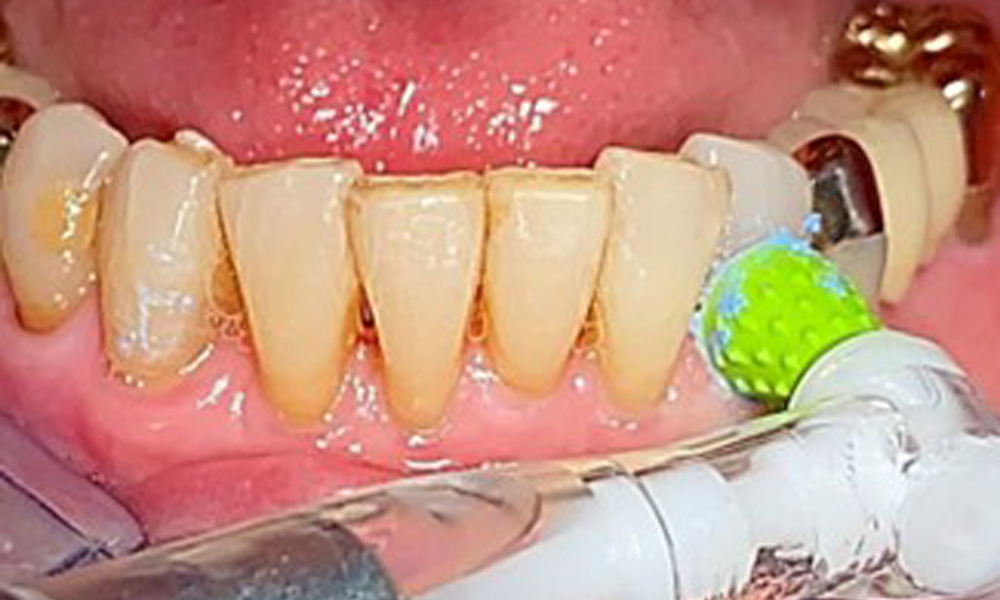

Für die Restaurationsränder und Zahnzwischenräume und Implantatoberflächen kann das Pulverstrahlgerät mit einem niedrig-abrasiven Pulver zum Einsatz zur Entfernung von Biofilm kommen (Abb. 12). Durch selektives Polieren (Abb. 13) sollte eine Glättung aller weniger sensiblen Bereiche erfolgen, da die bakterielle Wiederanhaftung reduziert wird. (9)

Selektives Polieren in Rg. 33 (hier Proxeo Twist, W&H)

Abb. 13: Selektives Polieren in Rg. 33 (hier Proxeo Twist, W&H)

Eine Einbüschelbürste insbesondere für die Teleskope sind empfehlenswert (Abb. 8) und Interdentalbürstchen mit der passenden Größe sind der Patientin aufzuzeigen (Abb. 9). Die Patientin setzt diese Empfehlungen der häuslichen Mundhygiene seit vielen Jahren um und wird im Rahmen der unterstützenden professionellen Präventionssitzung bestärkt, dies weiterhin zu tun.

Darstellung einer Einbüschelbürste zur häuslichen Pflege für Implantate und Teleskope.

Abb. 8: Darstellung einer Einbüschelbürste zur häuslichen Pflege für Implantate und Teleskope.